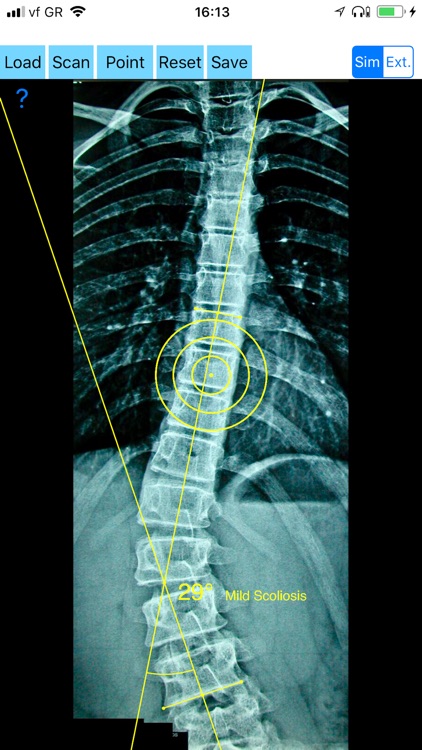

Cobb method is considered the standard for measuring curve size in scoliosis. Cobb angles are always measured from the superior end plate of the most cephalad end vertebra to the inferior end plate of the most caudal end vertebra in the curve. Meticulous line drawings and precise measurements is paramount importance in order to quantify the magnitude of spinal deformities and monitor the success or failure of treatment for scoliosis.

-Offers a very convenient way to determine the most accurate possibly way at once. By marking four points at the same X-ray, at each spine the App calculates the Cobb angle. In cases where values are out of normal ranges, the scoliosis is categorized according to measured angle as mild, moderate, severe. To simplify the process and to minimize inter-observer errors usually by not selecting the actual end vertebra, the app offers also in ext mode the ability to draw the vertical reference line through the patient’s sacrum and to identify more easily the end vertebrae s (ext method).